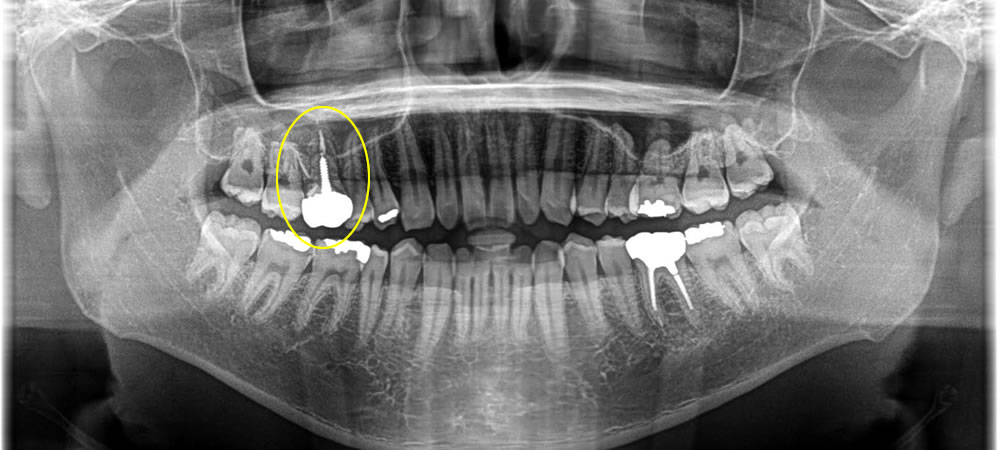

骨造成法を併用したインプラント治療の症例

年齢

性別

症例を見る